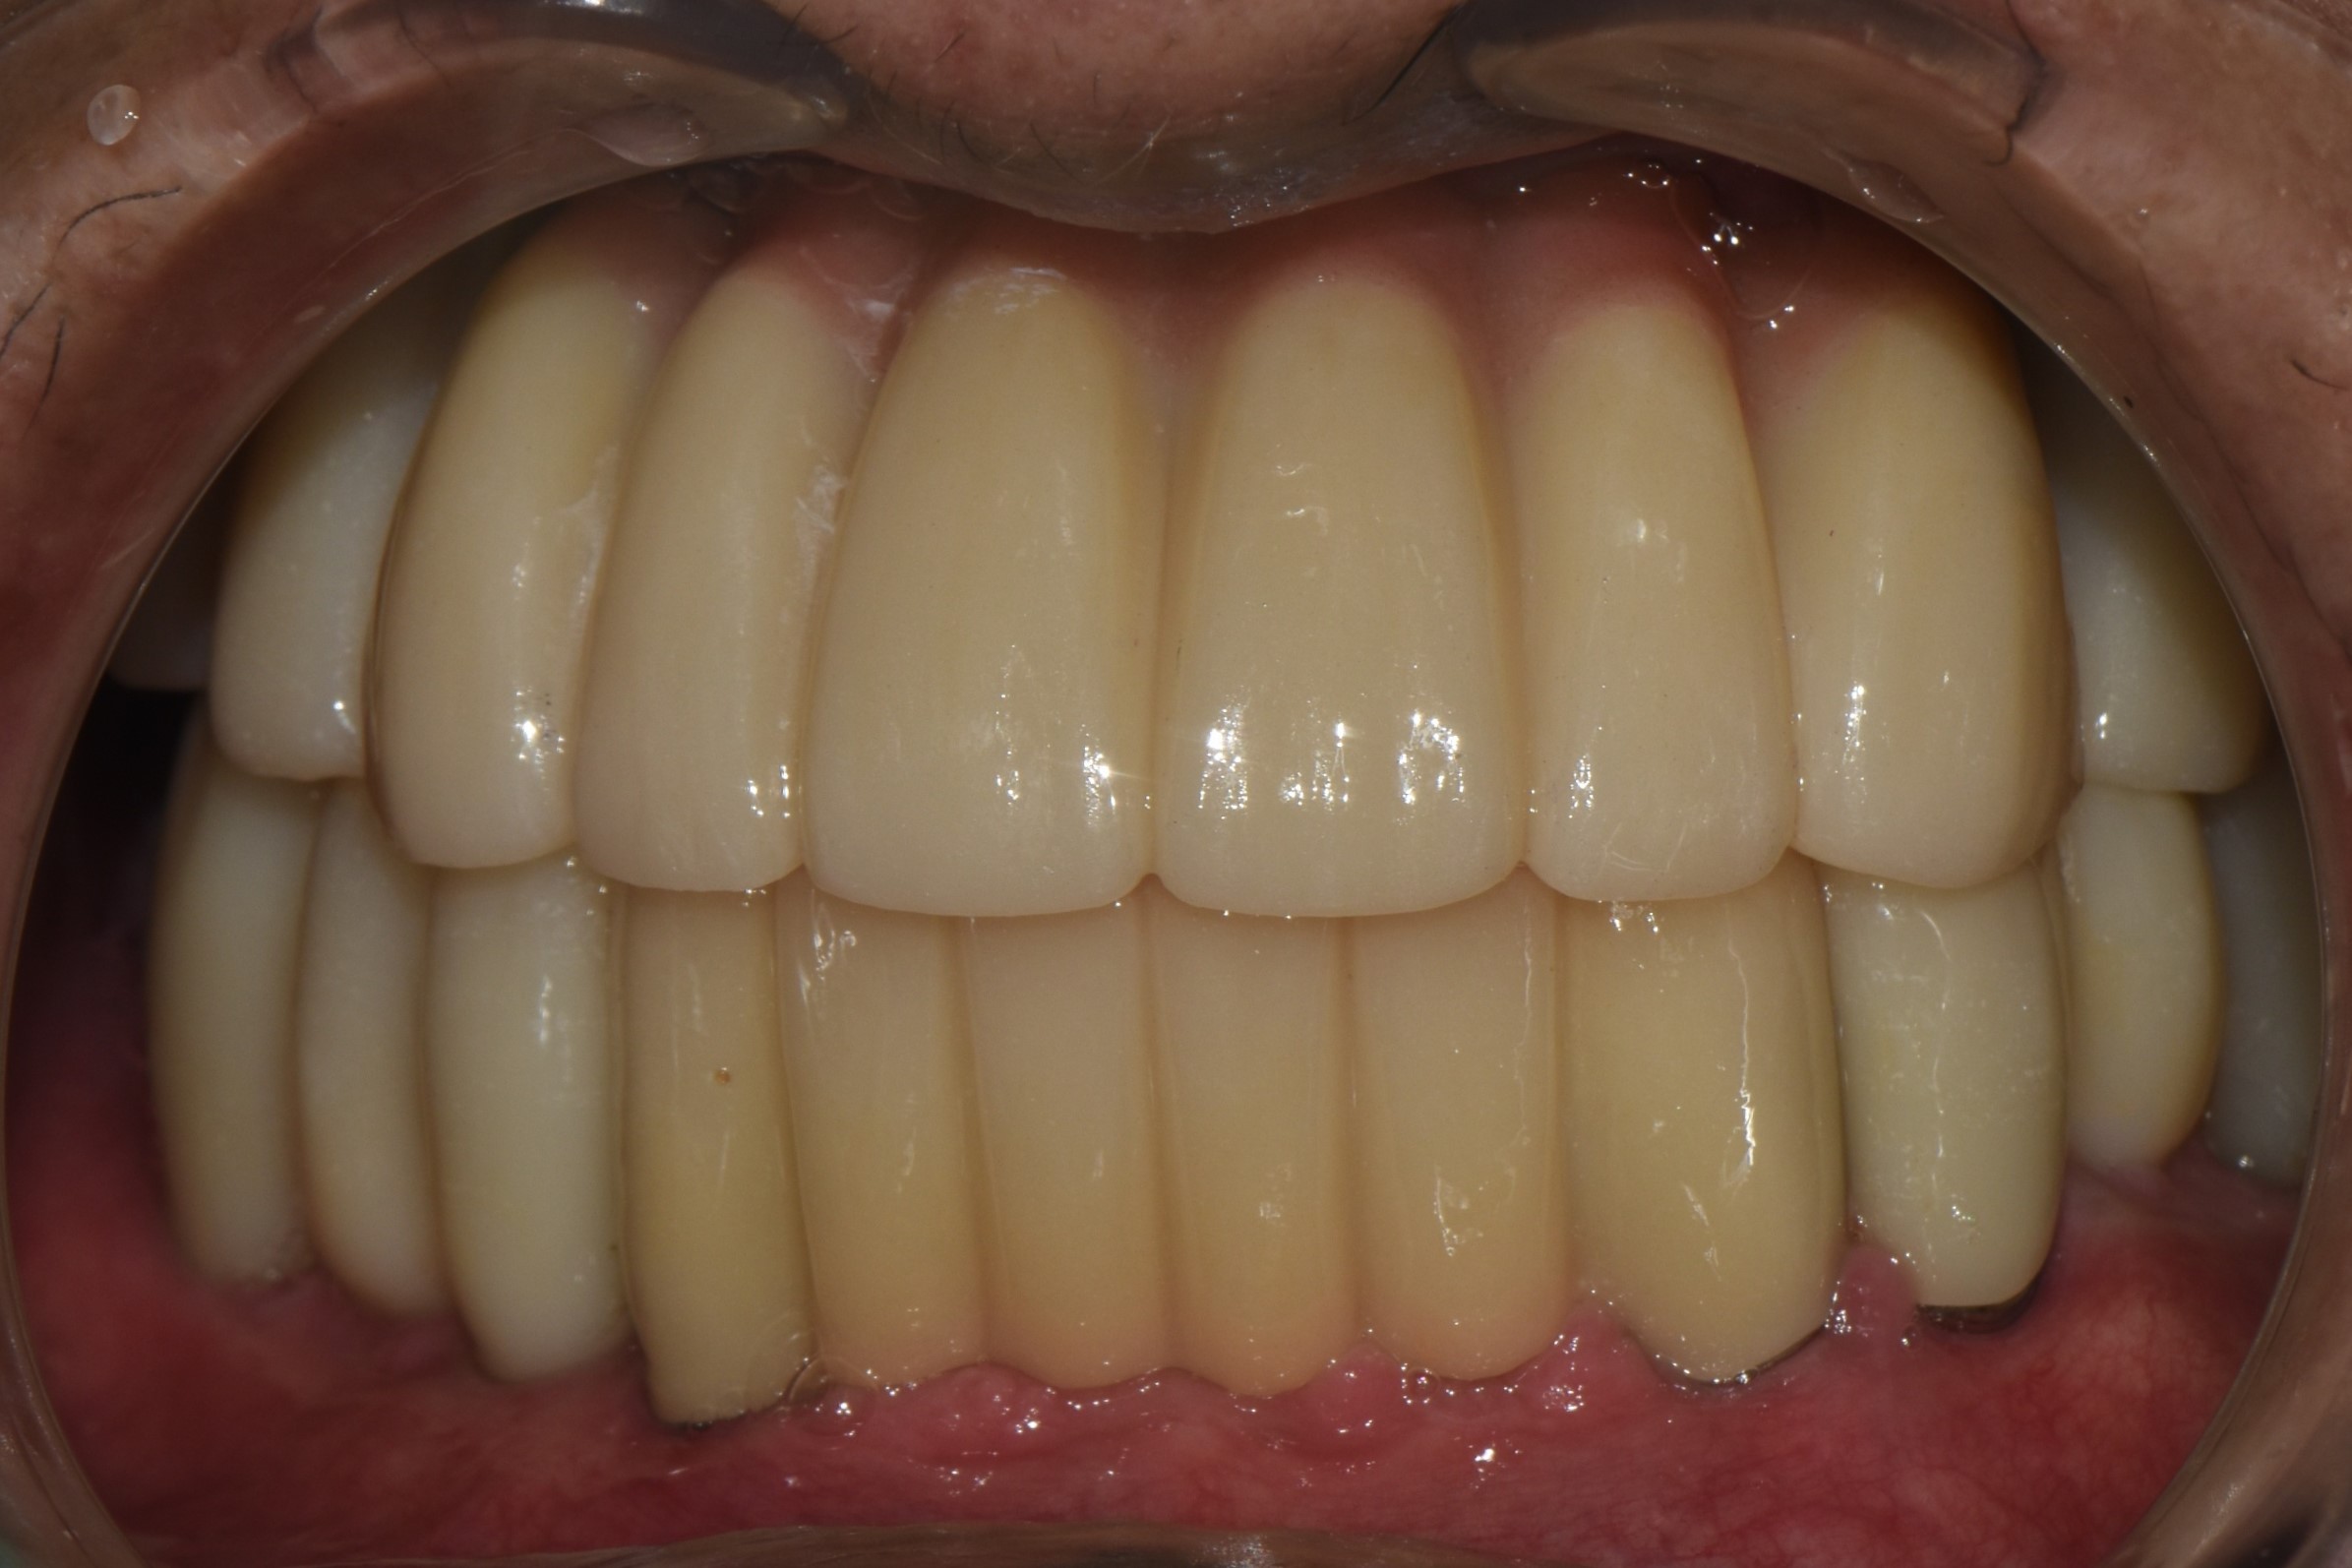

촬영일시: 2024.05.03

[ 치료기간: 2024년 05월 03일 ~2025년 03월 14일 ] ※ 365서울앞선치과의원의 모든 컬럼은 각 진료과 의료진이 직접 작성합니다. 365서울앞선치과의원 임상 케이스 게시물은 환자분께 의학적으로 정확하고 상세한 정보를 드리기 위해 각 진료과 의료진이 직접 작성하며, 모든 증례 사진은 본원 의료진이 직접 시술한 증례를 촬영한 것으로, 의료법 제23조, 제56조에 의거하며 환자분의 동의를 얻어 포스팅에 사용하였습니다. 또한 해당 케이스는 본 환자분의 치료 결과이며, 환자 상태에 따라 치료의 결과는 달라질 수 있습니다. |